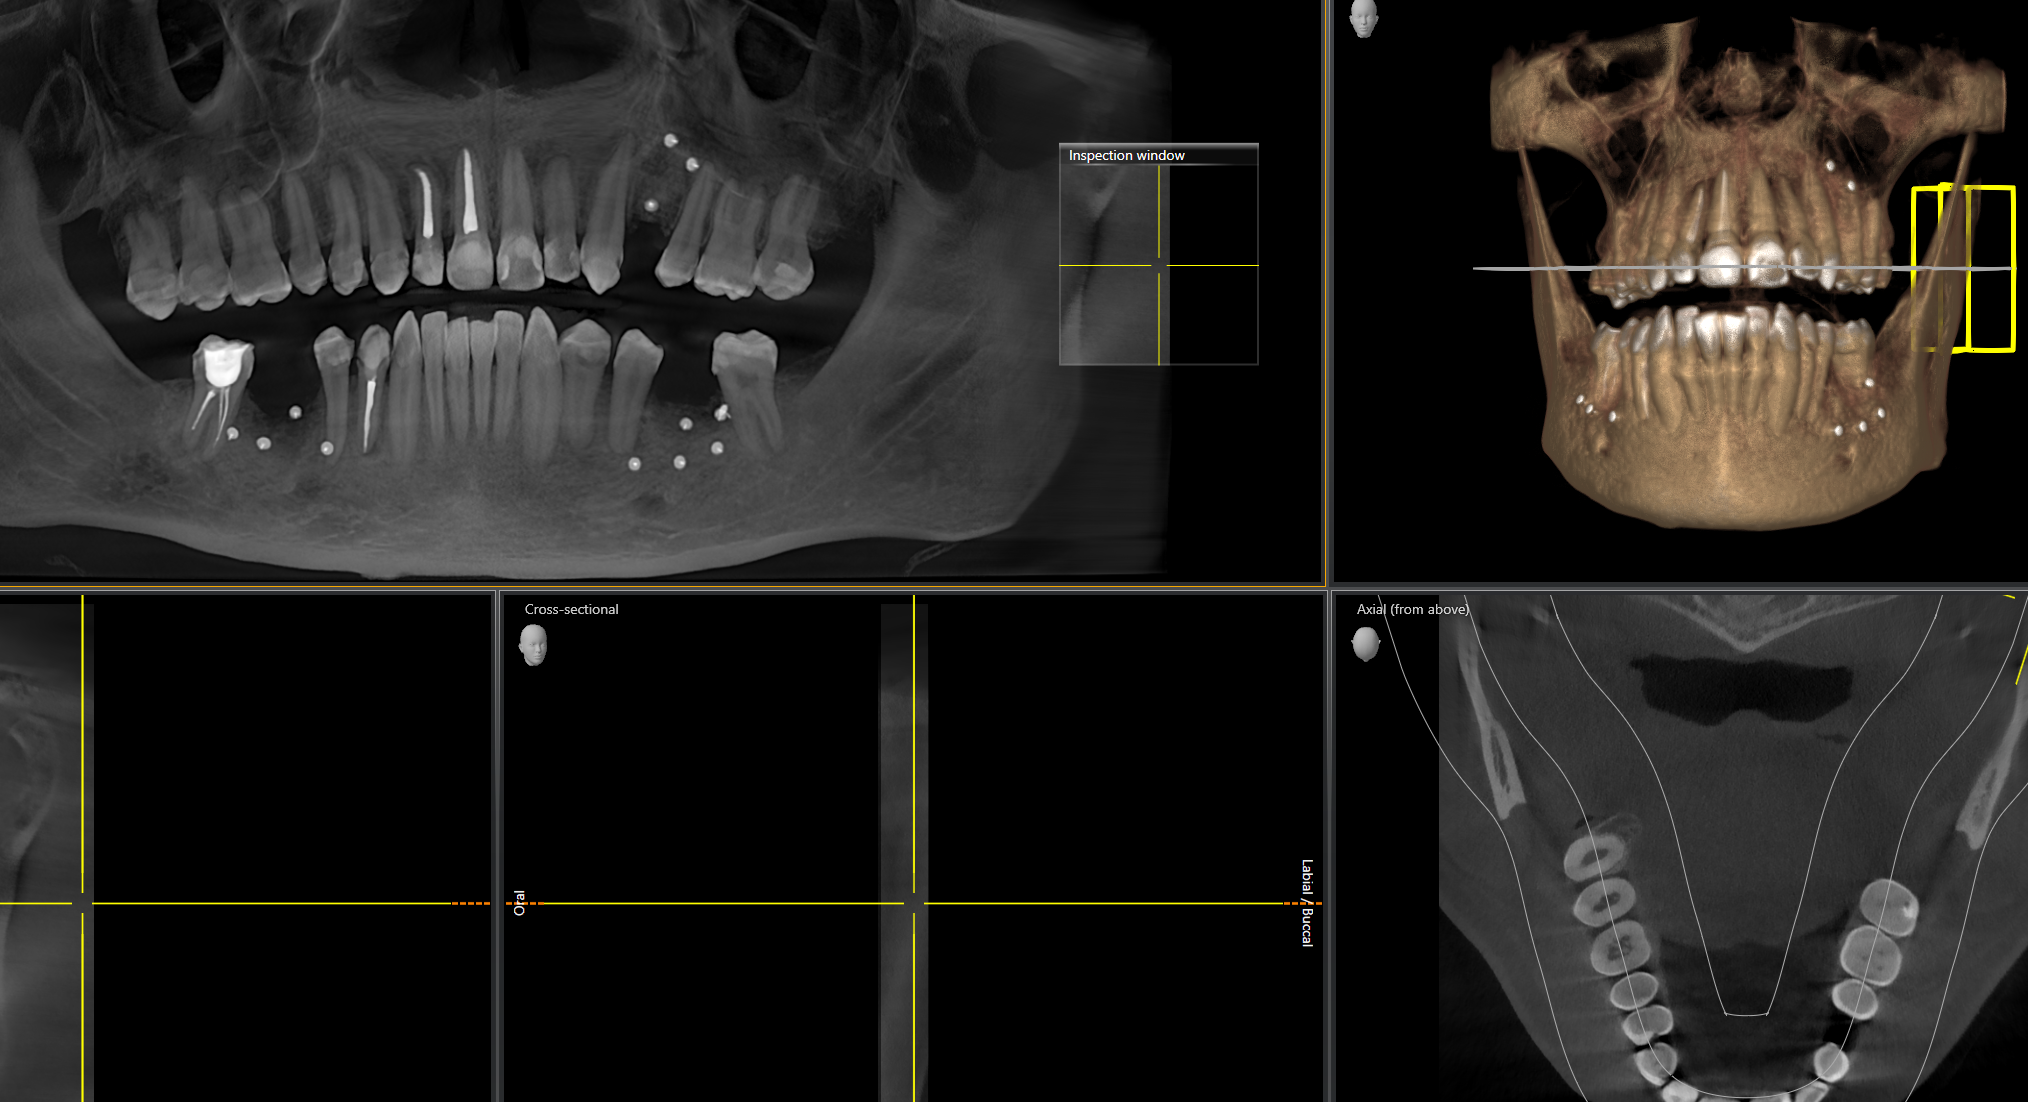

Кстати сами смотрите свои снимки перед брекетами и, если мало кости, то это хуёвая затея - можно без зубов остаться в итоге.

Ну и рекомендую сделать клкт, если не пригодится в этот раз, по крайней мере будет у тебя "паспорт" твоих зубов и каналов цена в пикассо около 3к.

Кстати, если мне выдали результаты КТ челюстей на диске, я могу с этим прийти в какую-то другую клинику за альтернативным мнением, или у всех свои форматы?

(на диске некий Planmeca Romexis Viewer - Romexis_Viewer_Win.exe для винды, Romexis_Viewer_OS_X.app - и папка data с результатами скана)